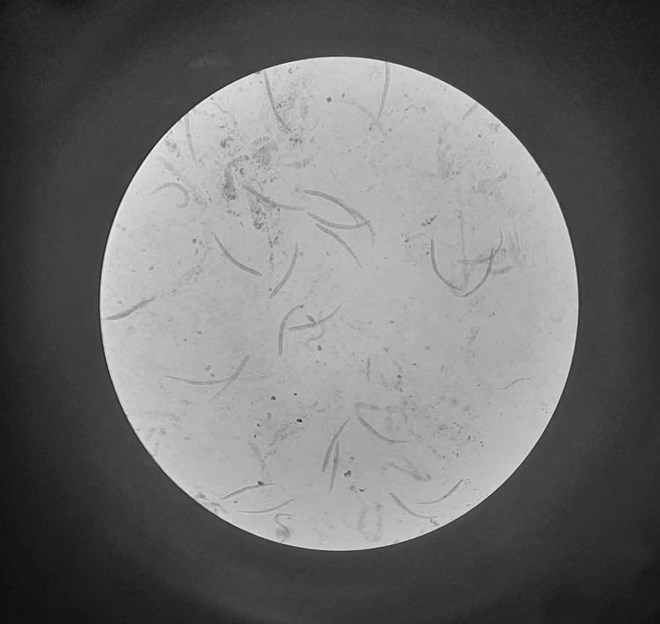

Hình ảnh giun lươn trong cơ thể người bệnh. Ảnh: BVCC

Tại bệnh viện, bệnh nhân được chẩn đoán suy gan cấp, rối loạn đông máu, K đại tràng. Xét nghiệm dịch dạ dày và dịch phế quản bệnh nhân có nhiều hình ảnh giun lươn, phù hợp bệnh cảnh lâm sàng, qua đó được chẩn đoán: Nhiễm giun lươn lan tỏa.